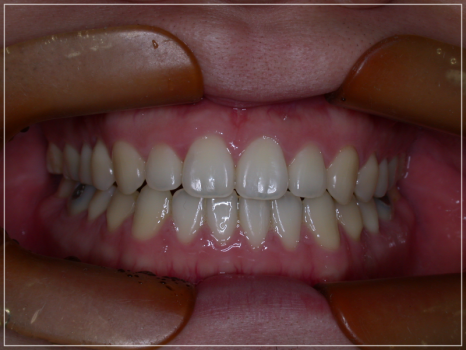

개방교합이 심해 장치 후 교정을 진행해야 하는 케이스입니다.

턱관절 급속 안정화 장치를 통해

퇴행성 관절염을 해결하여 더 이상

턱이 후퇴하여 개방교합이 생기지 않도록

안정화를 시킨 후 치아교정을 통해

입안다물어짐을 개선하고

없애주는 원리의 방식인데요.

추후 위와 같은 상태가 다시 생겨나는 것을

막기 위해 트랙션장치를 착용함으로써

교정된 치열을 유지시키면서 다시 문제가

생겨나는 것까지 효과적으로 예방해주어

두가지 목적으로 활용이 가능하답니다.

가지런히 정돈된 치열과 개방교합이 개선된 모습

또한, 단지 트랙션만 진행하는 것과는 달리

보다 안정적인 과정으로 대부분 일정하게

개선이 가능하다는 장점이 있는데요.